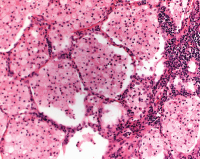

Eosinophilenpneumonie

Abbildung 6: Eosinophilenpneumonie, einer der seltenen Befunde bei EVALI (H & E, X 400)

Keywords: eosinophile PneumonieHistologisches Präparat